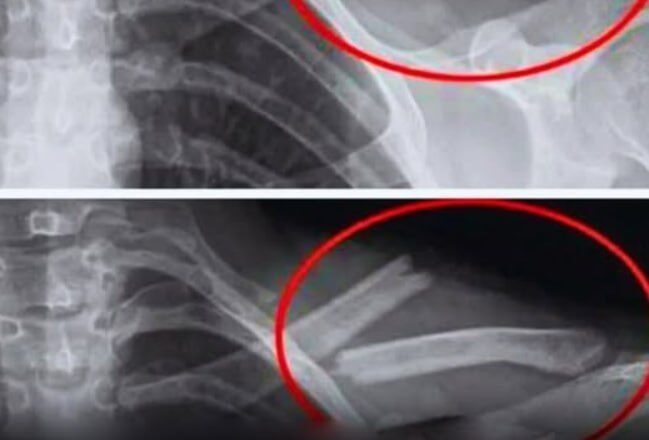

Дослідження показують, що надмірне вживання соди призводить до зниження щільності кісток, особливо у жінок. Іншими словами, ваші кістки слабшають… іноді без будь-яких симптомів, доки не станеться перелом.

Дослідження, проведене в США за участю 2500 жінок, показало, що ті, хто регулярно вживає колу, мають меншу щільність кісткової тканини стегон. І робили це несвідомо.

Дослідження, проведене серед дівчат-підлітків, також виявило зв’язок між споживанням газованої води та підвищеним ризиком переломів.